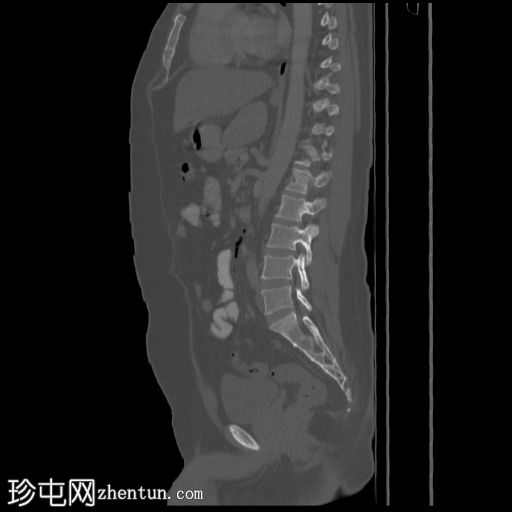

矢状位骨窗

D12椎体陈旧性前压缩性骨折,无移位。